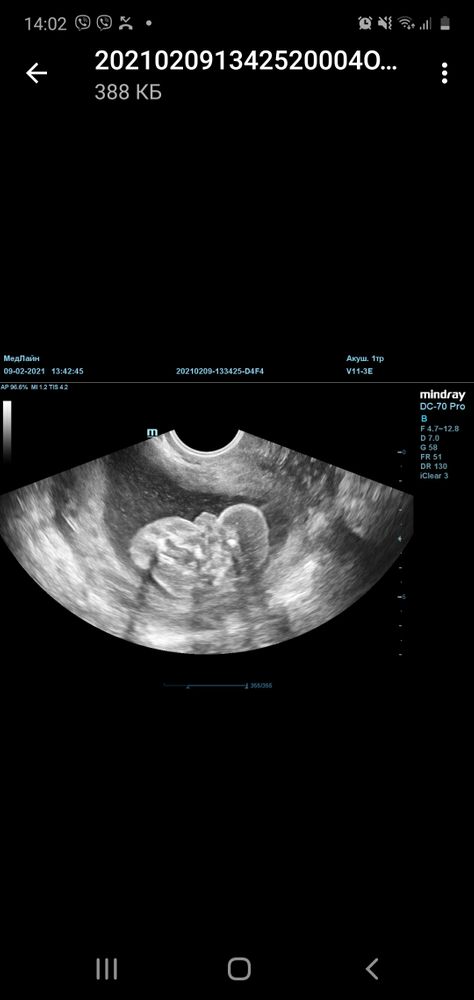

Это девочка?)

Девочки, всем привет! Сегодня ходила на скрининг в 20 недель. Пол смогли увидеть только вагинальным датчиком. Сказали девочка . Посмотрите, пожалуйста, это точно девочка?😂 не яички ли

К сожалению у меня нет фото,но в 20 недель прям отчётливо писюн показали)))) У вас больше на девушку похоже)))Не думаю,что 20 Нед ошиблись

Яички в мошонку отпускаются почти перед рождением малыша) а тут вроде пирожок🤭🤭🤭